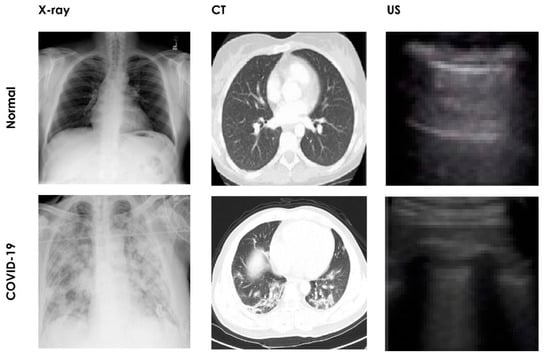

Figure 1.

Pictorial representation of normal and COVID-19 affected lungs.

The development of an automated COVID-19 detection system based on chest X-ray imagery requires labeled images of normal and COVID-19 cases so as to train the system to differentiate healthy persons from COVID-19 patients. To test the system with an independent test dataset and to enhance its efficacy, it is necessary for these datasets to be made available publicly. With large datasets, it is possible for researchers to cross verify existing AI models before installation in hospitals or testing centers. Hence, medical images such as chest X-ray, CT, and lung US images are essential for the development of an automated COVID-19 detection system. Many researchers have of their own volition or in collaboration with hospitals, aggregated the COVID-19 datasets with various imaging modalities and released them publicly to assist research communities. Figure 4 shows examples of several chest images from publicly available datasets.

Figure 4.

Sample images using various medical image modalities.